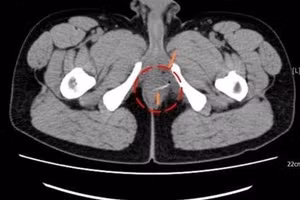

GD&TĐ - Một mảnh xương nhỏ xuyên thủng đại tràng, găm thẳng vào gan của người đàn ông 58 tuổi tại TPHCM, tạo thành ổ áp xe lớn, gây nhiễm trùng ổ bụng.